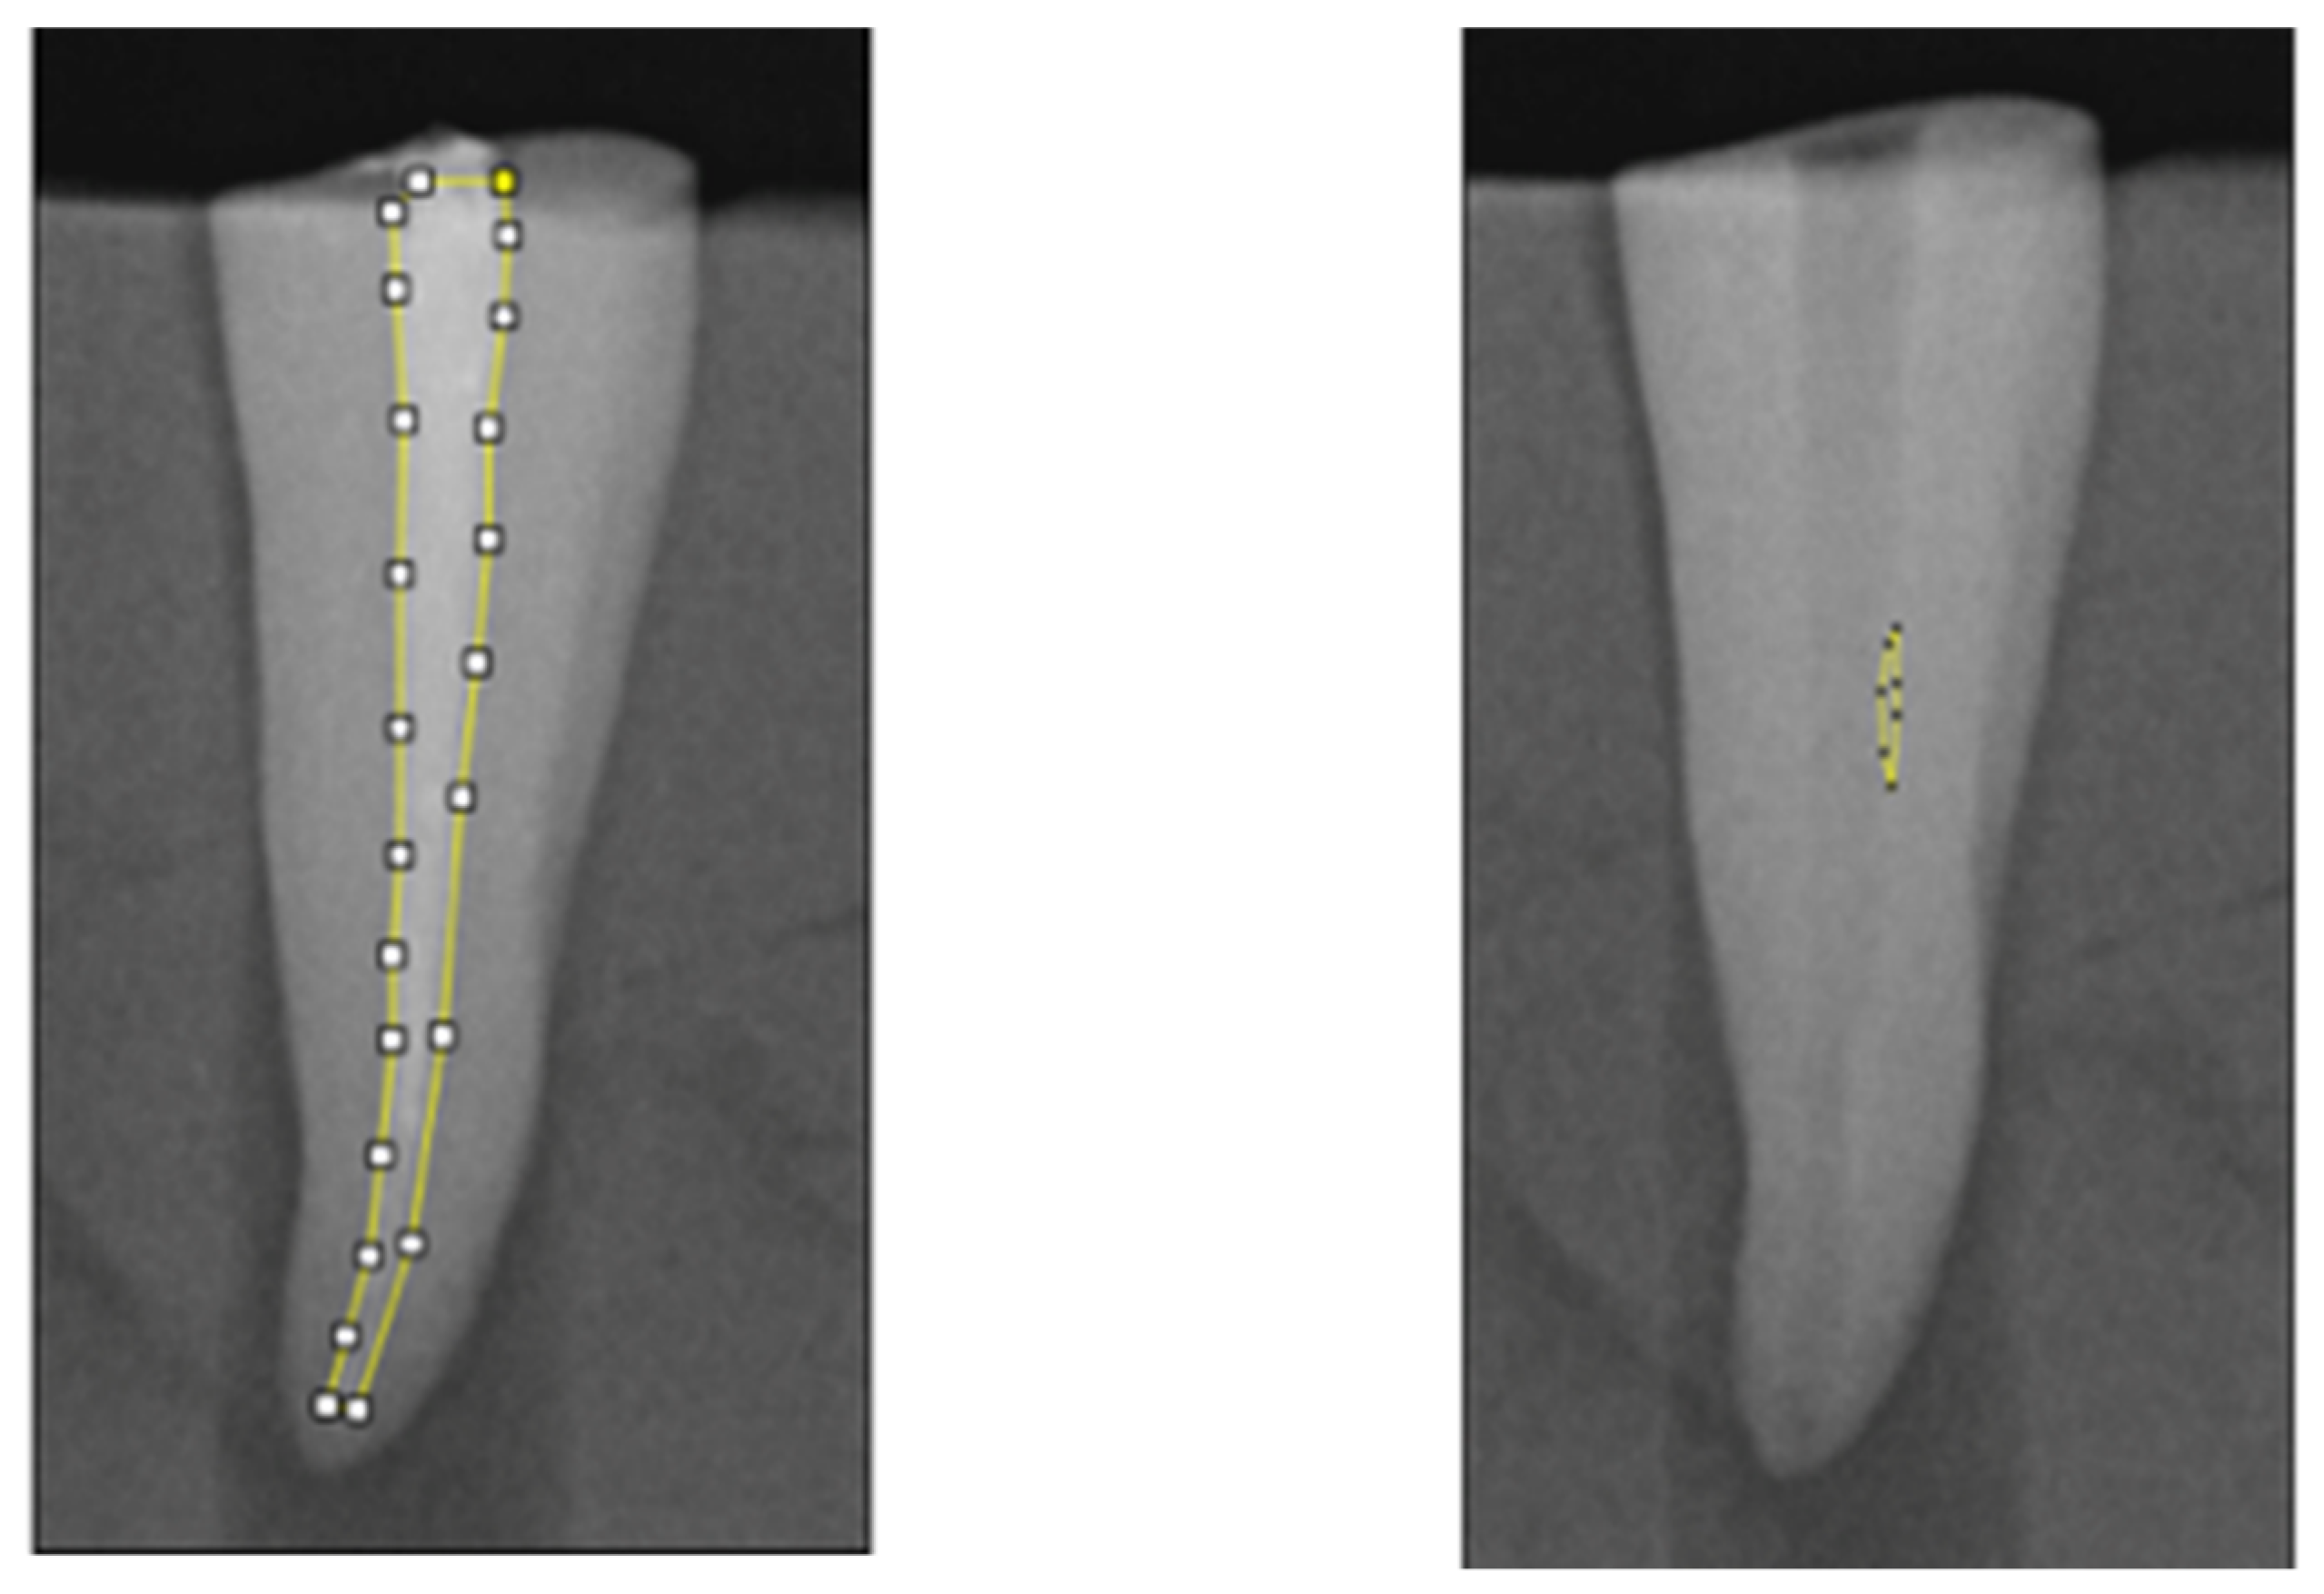

2.4. Radiographical Analysis

Figure 2. Methodology for quantitative analysis of the canal area and residual canal area using ImageJ software on periapical radiographs. A periapical X-ray was taken at the end of the canal obturation. On the digital image obtained, the canal area and the obturation material area were calculated by manually delineating the boundaries of the region of interest. Periapical X-ray image taken at the end of the retreatment. Residual materials are manually highlighted. The obtained image was used to calculate the canal area and the residual area, divided by root thirds.